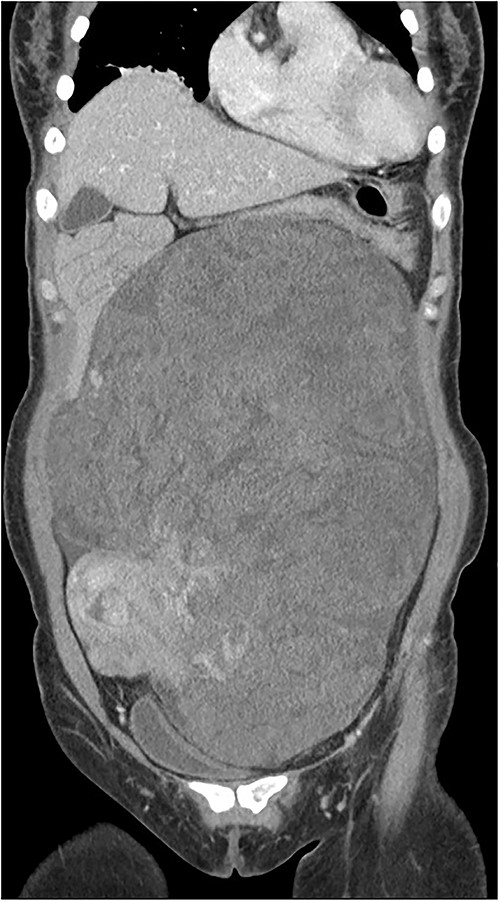

Computed tomography (CT) of the enhanced upper abdomen showed a well-defined, heterogeneous, focally enhanced soft tissue (30 × 20 × 9 cm) occupying the abdomen and pelvic cavity. The bowel and the uterus were displaced by the mass (Fig. 1). Magnetic resonance imaging of the pelvis showed that this mass was independent and not a lymph node mass but a type of retroperitoneal sarcoma. Positron-emission tomography–CT showed that a huge mass (32 × 23 × 12 cm) in the abdominopelvic cavity, with mostly heterogeneous mild 18F-FDG uptake.